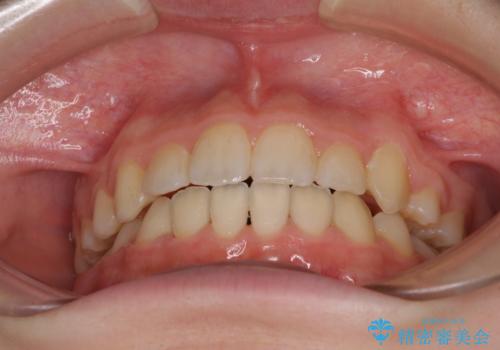

下顎の乳歯は永久歯と比べて幅が大きいため、抜歯した場合のスペースが大きく、治療には長期間を要することが一般的です。

今回の患者様は中学生ということもあり、成人の患者様と比べ動きが速く、2年間で治療を終えることができました。